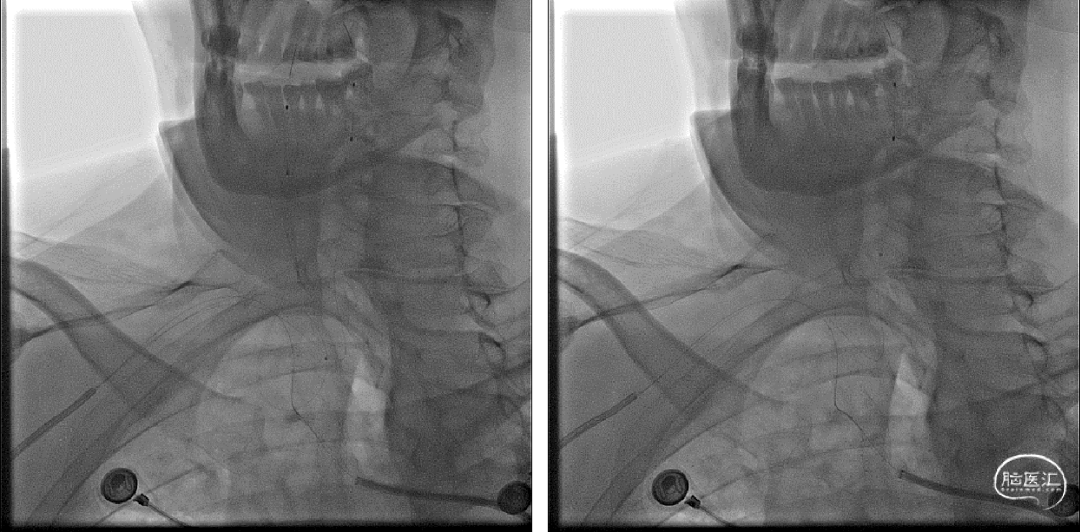

术后三日复查CTA如下,复查CT可见支架位置及形态良好,支架内及远端血流良好。

术后三天CTA